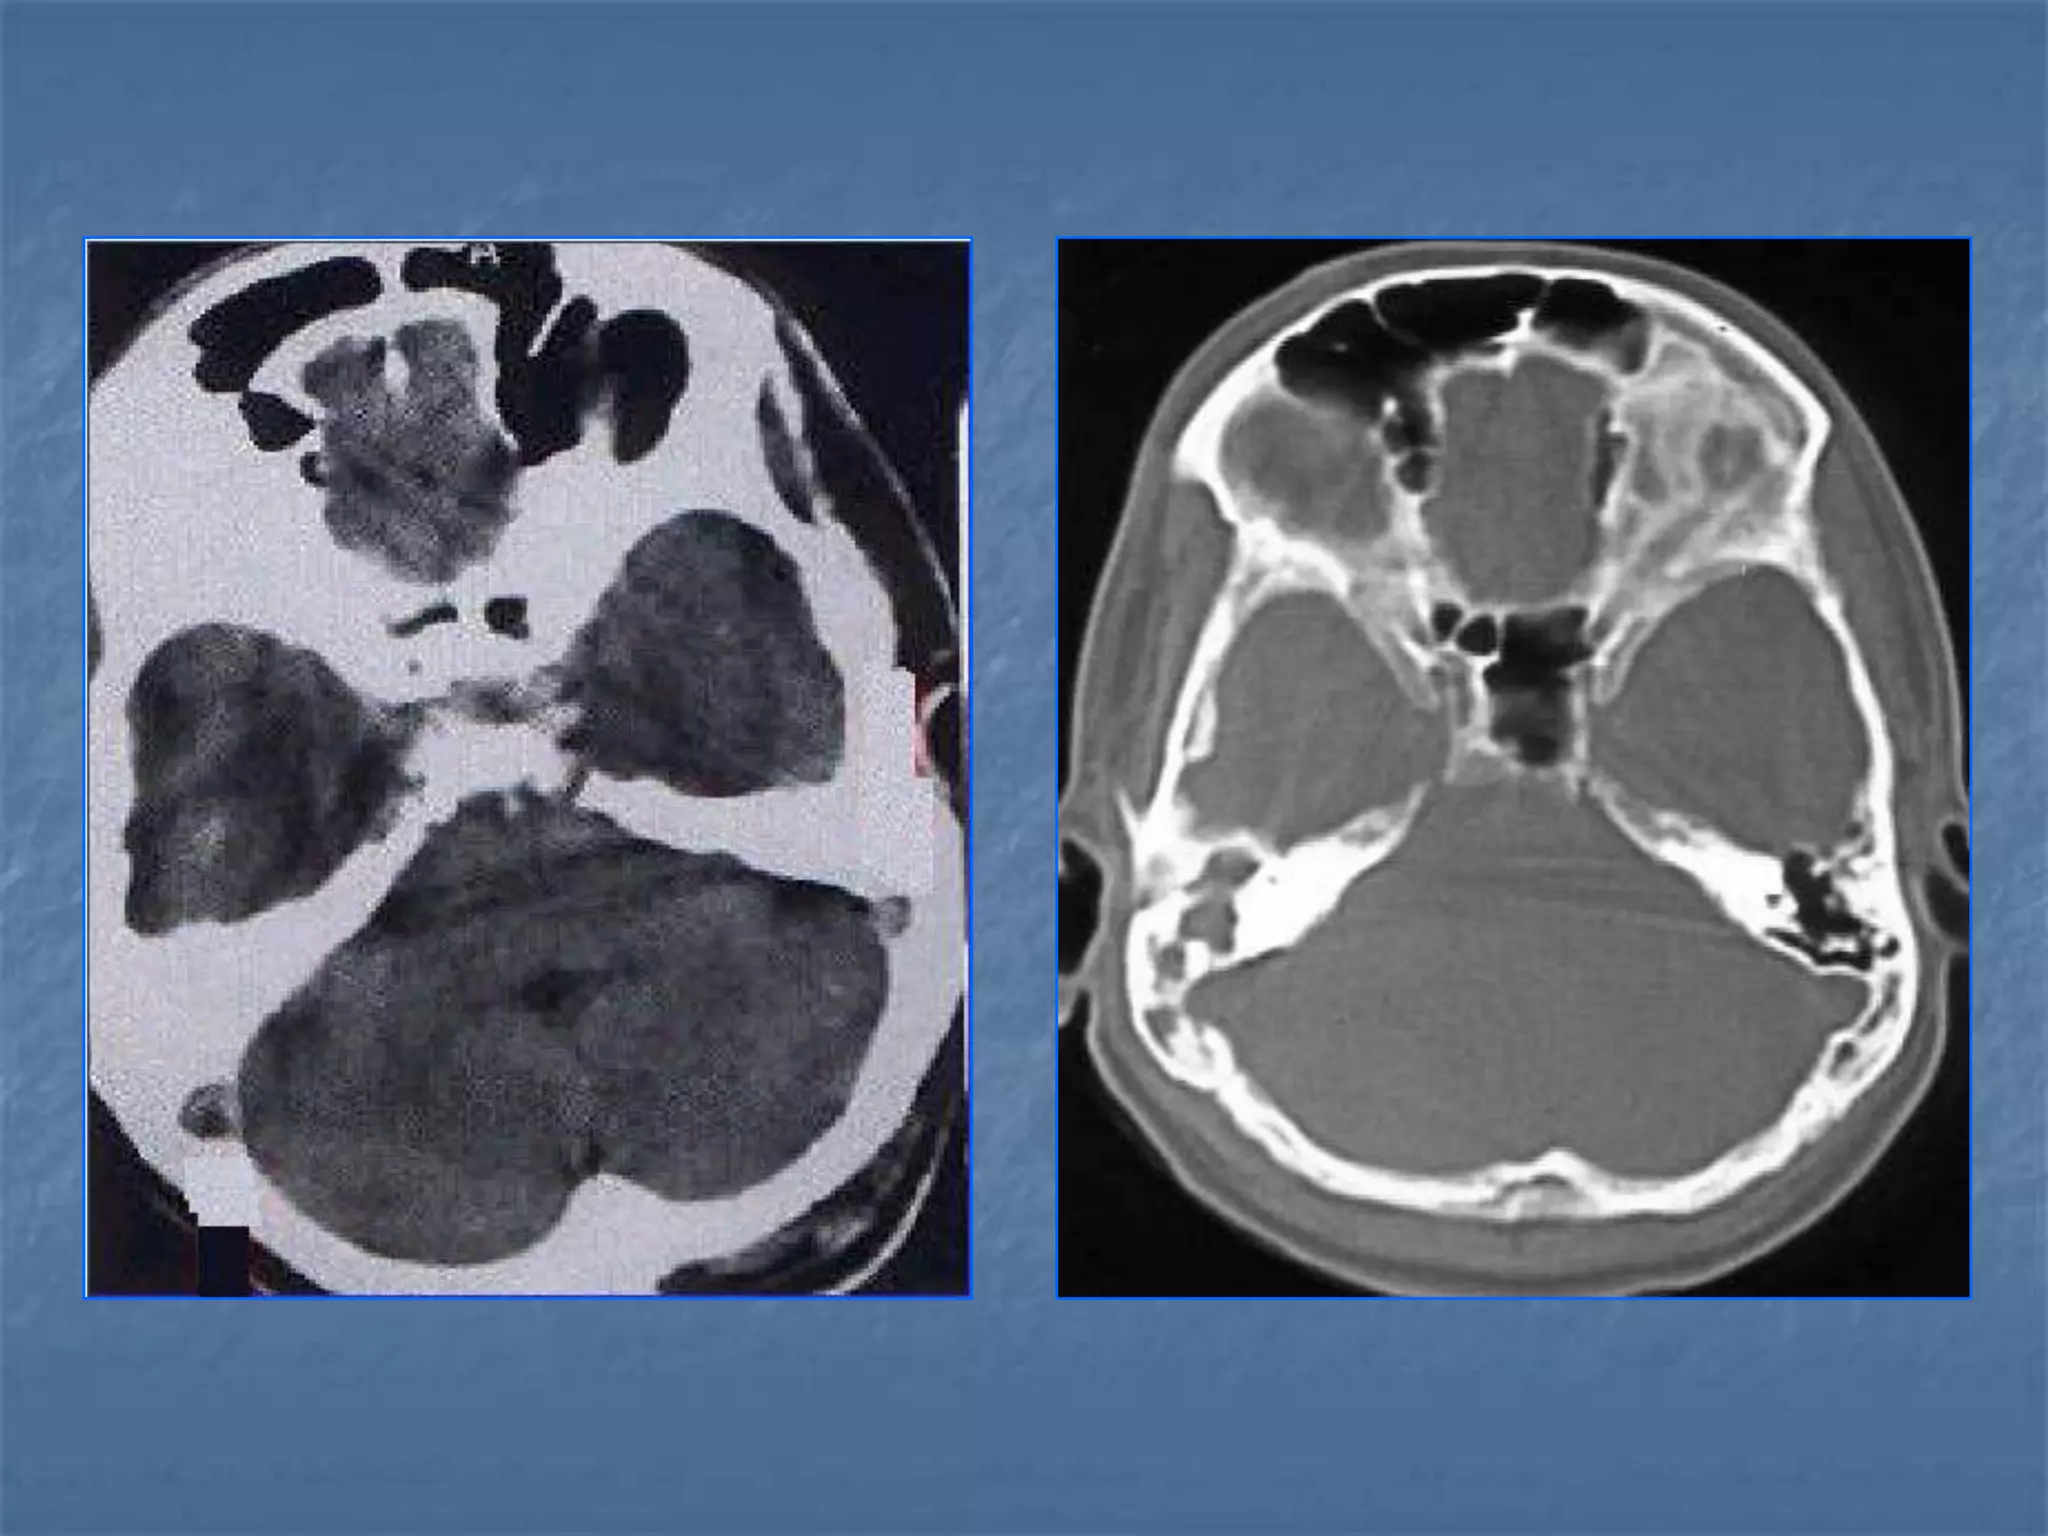

How the CT study is usually planned…

 Thinner sections

are studied

through the

posterior fossa